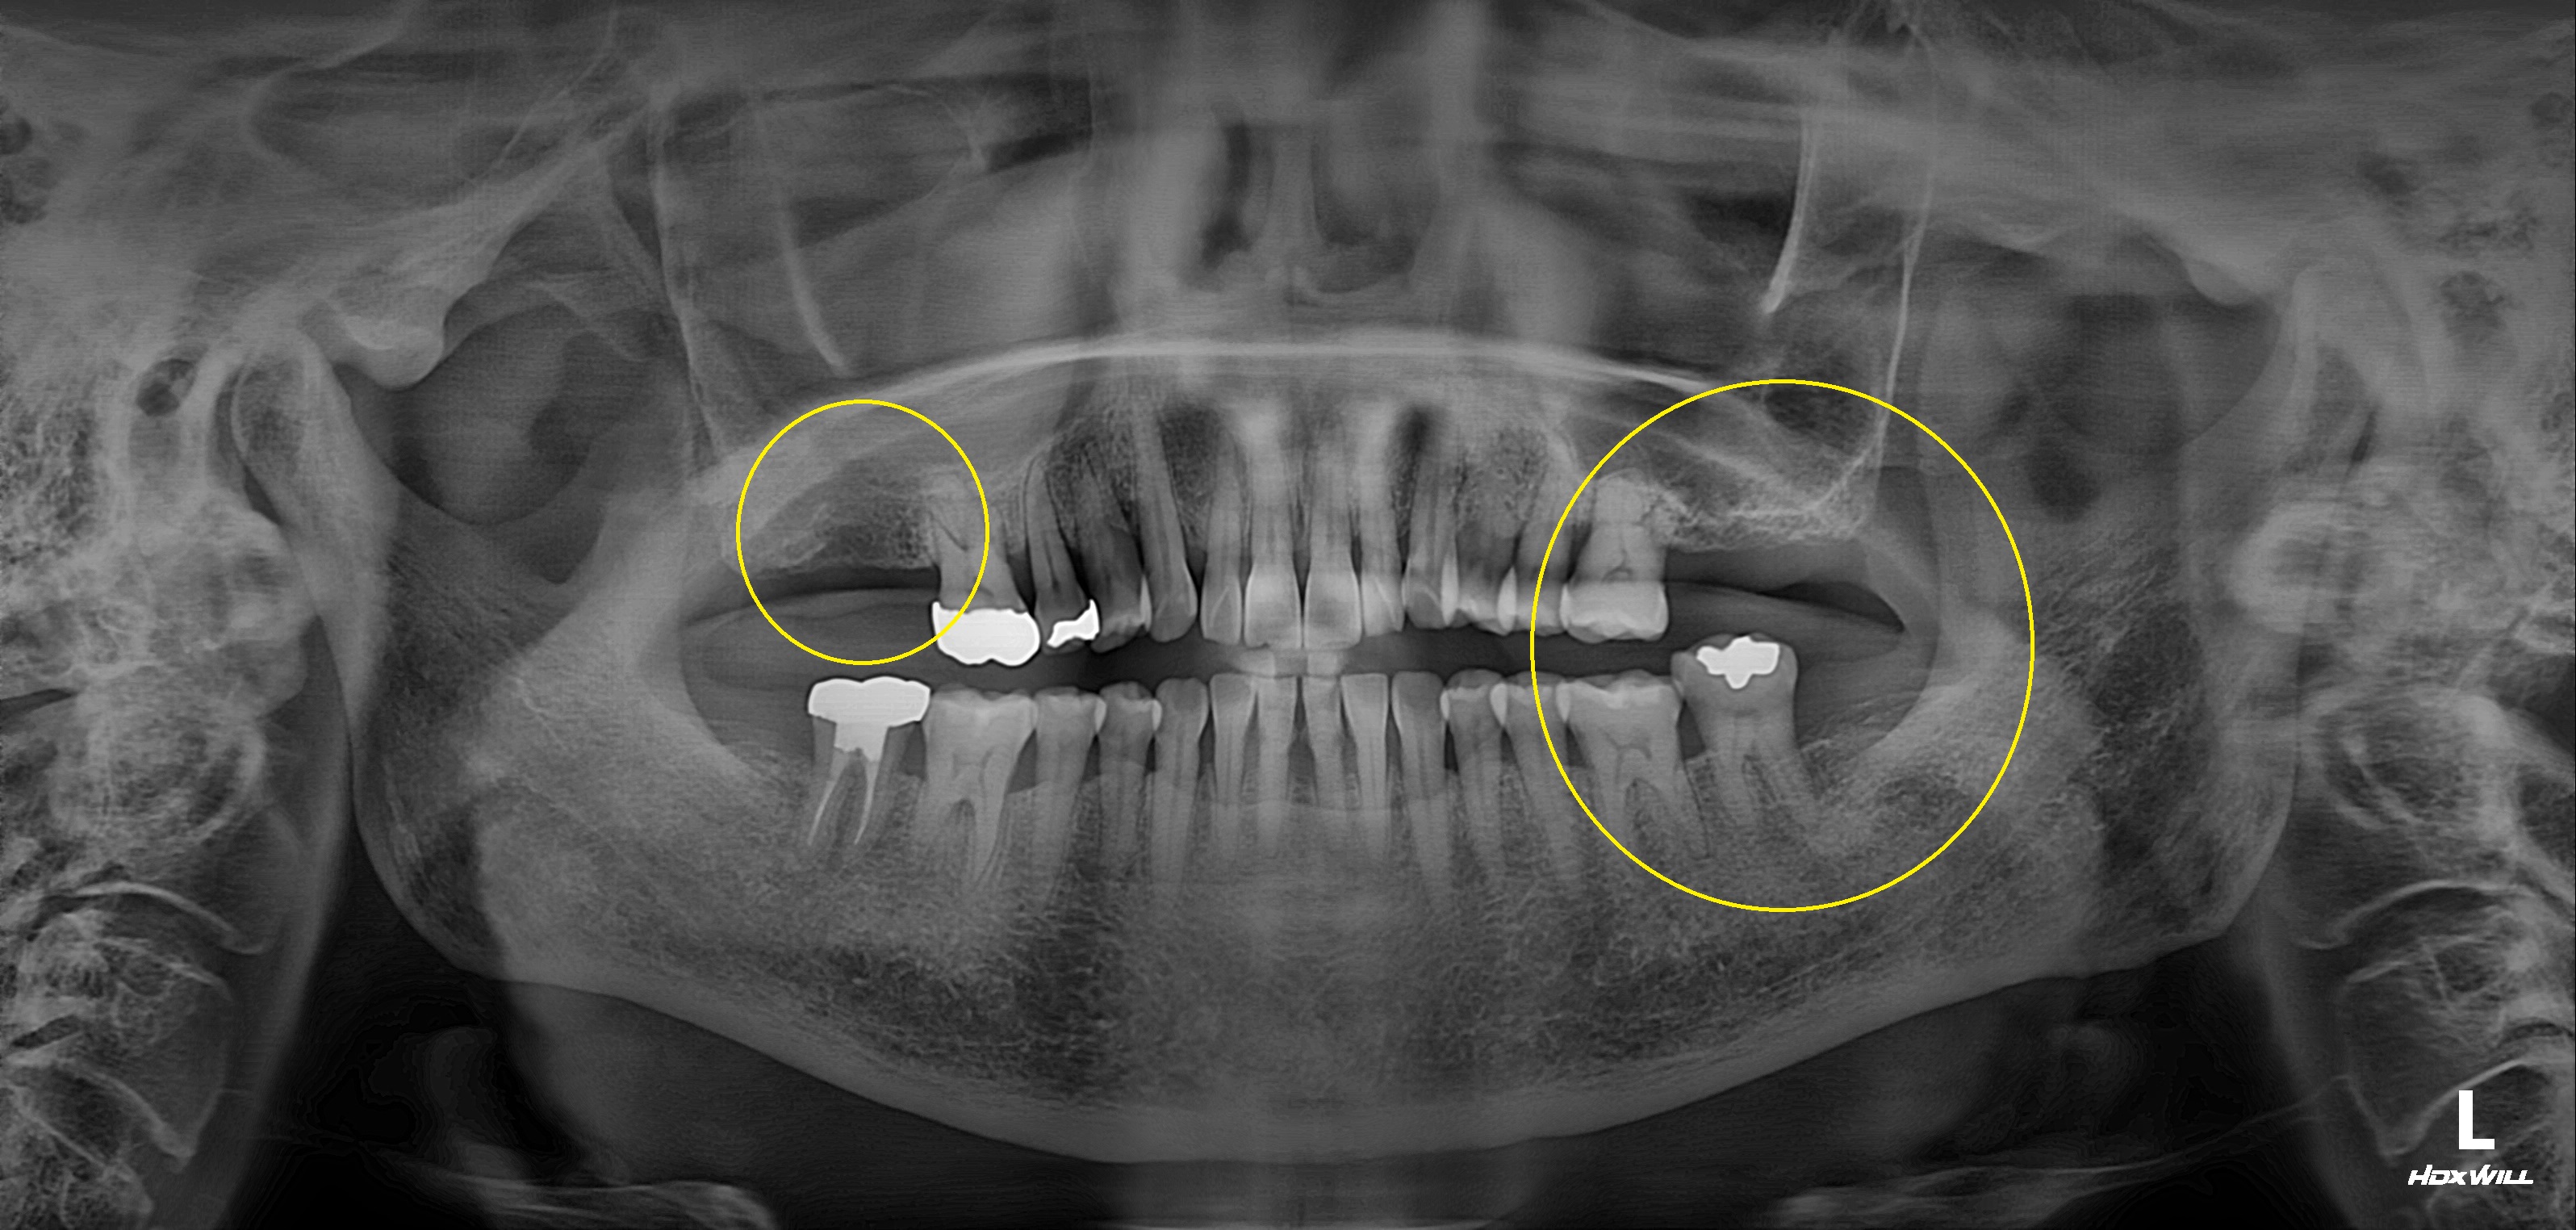

완전매복치사랑니 발치 + 구치부 임플란트 사례

전후사진